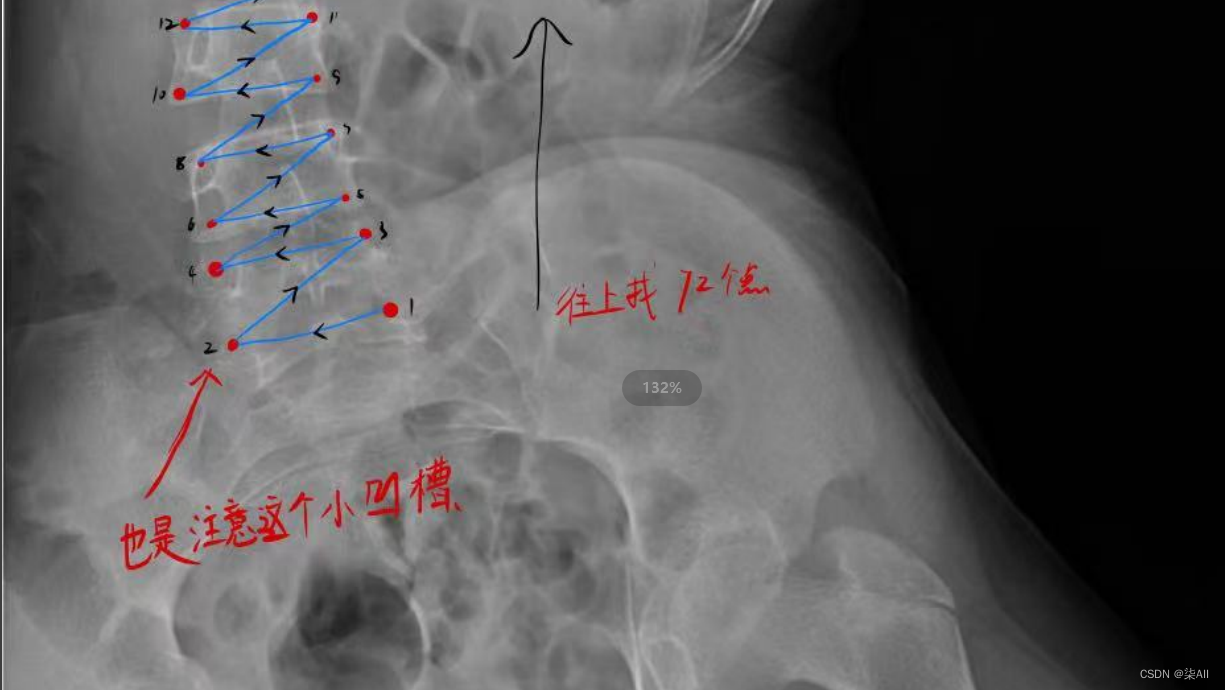

5、标注结果注意

(0) 最后一个椎体看不清的话,最后一个肋骨连接的就是胸12 也就是T 12 ,下面那个就是L1(腰椎1),往下数五个就是 最后一个腰椎

(3)像这种椎骨不要变化太大,一般都是底下的椎骨大一些,往上逐渐减少,就因为看不清,所以得这样表

还是有很多问题的,这种计算cobb角肯定有问题,最后一个椎骨看不清,那画的线就与上一个椎骨平行,尽量平行标,要不然后面自动生成cobb角,误差很大,这样肯定不行,注意一下,认真一些,要不然得返修几次,不如好好弄,还节省时间

(6)你看这种58这种点,咱们可以往外标一点,或者把60缩一些